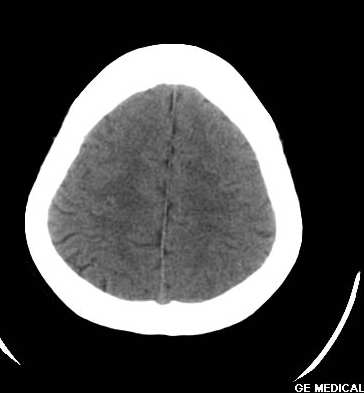

脑外伤患者,无外伤性改变

颅内脂肪瘤系因隶属于中胚层的脂肪掺合进正在关闭的神经管之中,绝大多数见于胼胝体膝部,肿瘤较小;偶尔可发生在整个胼胝体,肿瘤较大。颅内脂肪瘤也可见于四叠体池,鞍上池,大脑脚池以及桥小脑角池。约有50%的中线脂肪瘤并有胼胝体发育不全,但是,胼胝体发育不全很少并有脂肪瘤。胼胝体脂肪瘤有症状的仅占一半,主要为癫痫,痴呆,头痛,半身不遂。癫痫系因脂肪瘤使邻近的纤维性结缔组织浸润到周围脑组织所致。脂肪瘤占位效应不明显,由于它浸润性生长,有时可造成对邻近血管如大脑前动脉的包绕,可影响正常脑脊液通路而导致脑积水。

颅内脂肪瘤少见,占颅内肿瘤的1%以下。有人认为不是肿瘤,而是原始脑膜组织的畸形。好发于胼胝体及其周围。胼胝体区脂肪瘤多并发于胼胝体发育不良。瘤体呈圆形或分叶状,大小不等,境界清楚。ct上,病灶呈脂肪密度的圆形或分叶状肿块,周边可见弧形钙斑。无瘤周水肿。无强化。本例发生于胼胝体区低密度肿块,ct值-60,应是典型的胼胝体区脂肪瘤。